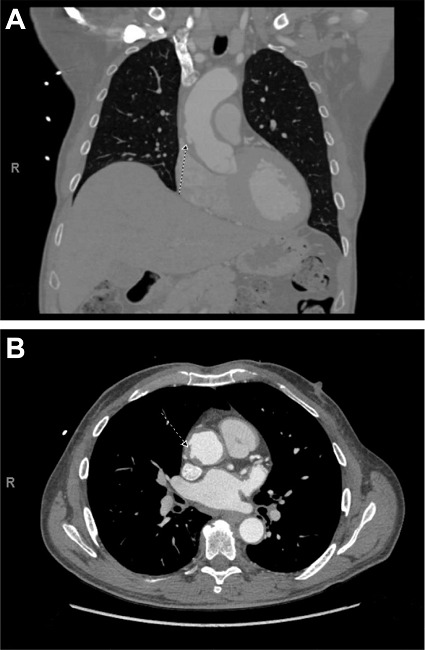

The patient was hypertensive at presentation, with acute, left-sided, chest pain unresolved with intravenous esmolol and nicardipine. Computed tomography (CT) angiograms revealed thickening and irregularity of the ascending aorta with multiple intimal ulcerations and an IMH (Figure 1) requiring urgent surgery.